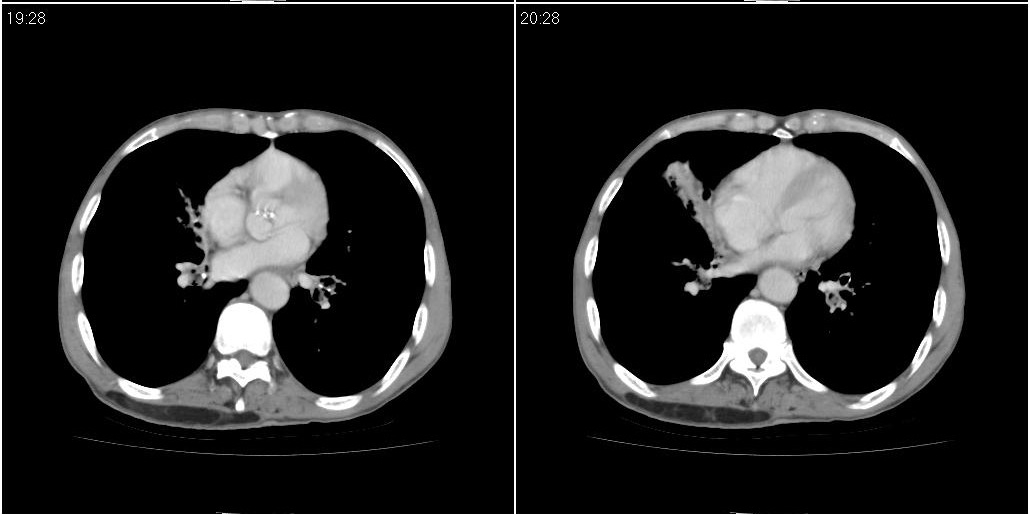

标题: ct增强:

右肺中叶阻塞性不张及肺炎,高度怀疑支气管占位,建议纤支镜检查!

考虑右肺中叶感染。左肺下叶支扩。

右中肺阻塞性炎症,建议纤支镜!双下支扩感染。